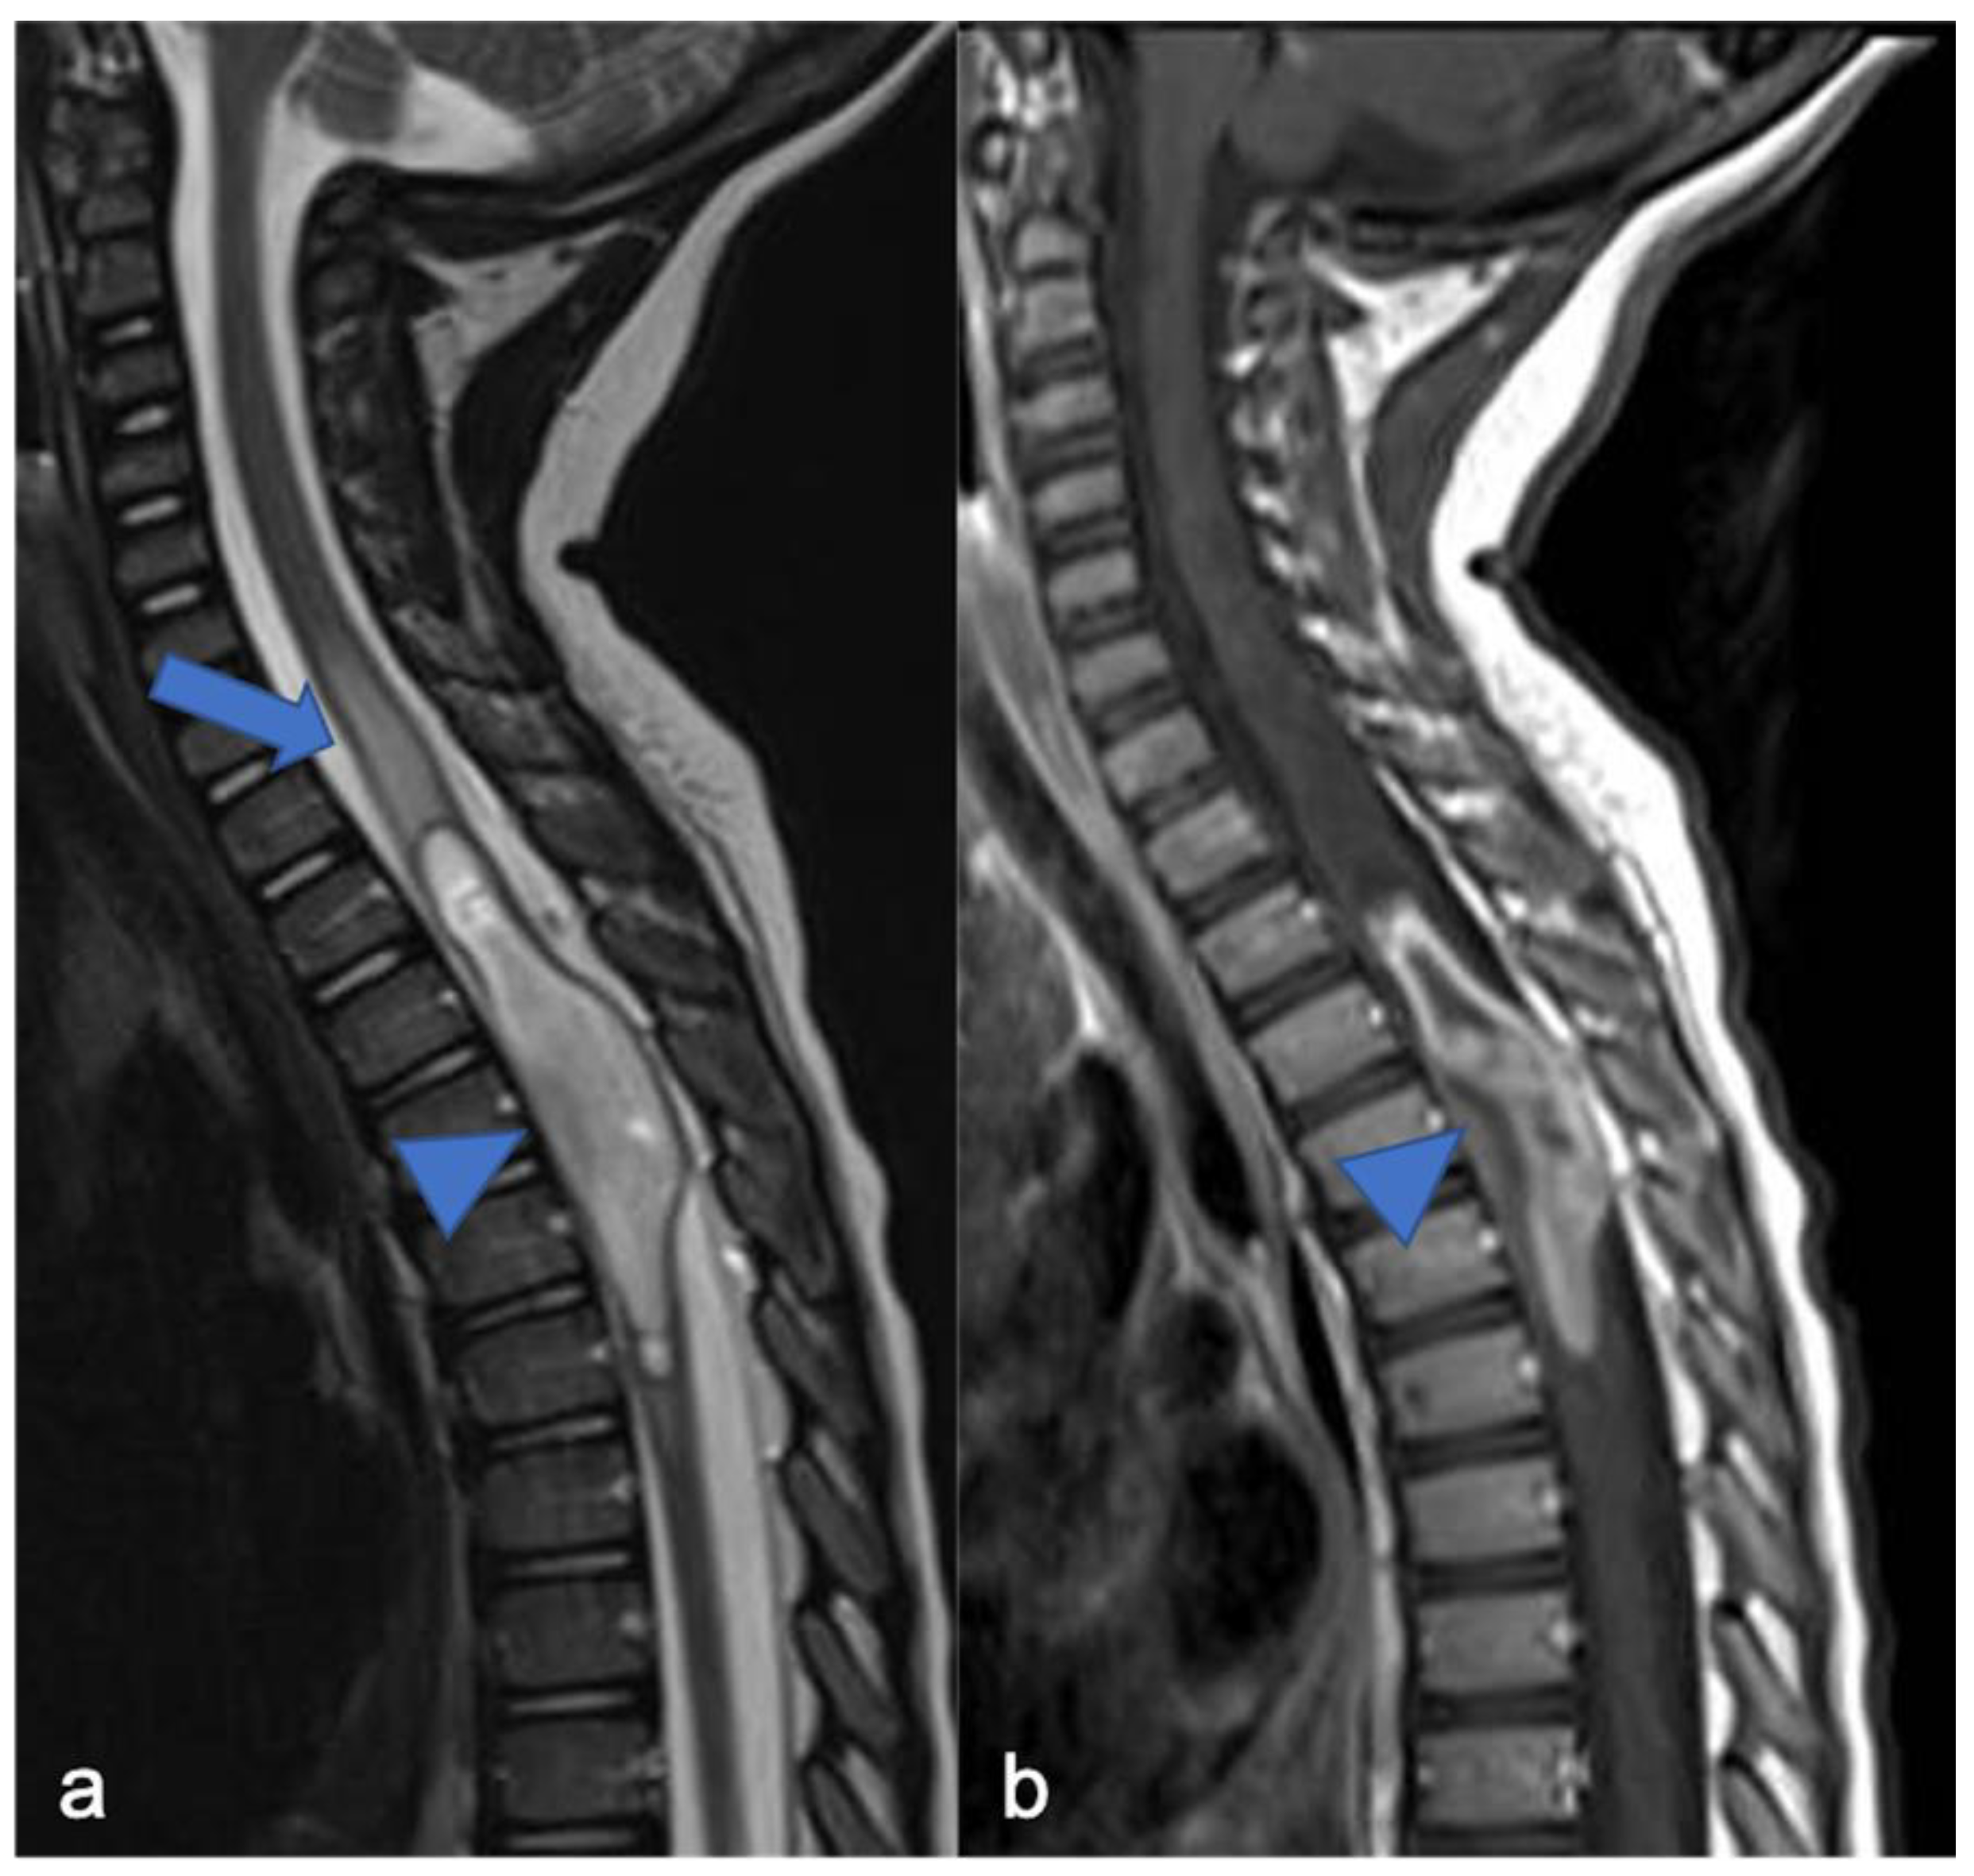

Figure 3.

High-grade glioma with H3K27M mutation in a thirteen-year-old child. Sagittal T2-weighted (a) and post-contrast T1-weighted (b) images demonstrate swollen appearance of the cervical cord characterized by T2 mild hyperintensity (arrow) and poor enhancement (arrowhead).

Figure 4.

Sagittal T2-weighted image (a), post-contrast T1-weighted (b), DWI (c; T10-T11) and DSC (d). High-grade glioma with cervical–thoracic epicenter and holocordal involvement of the spinal cord in a two-year-old child. The neoplasm is characterized by inhomogeneous enhancement. Components with restricted diffusion (arrow) and increased rCBV (arrowhead) are shown.